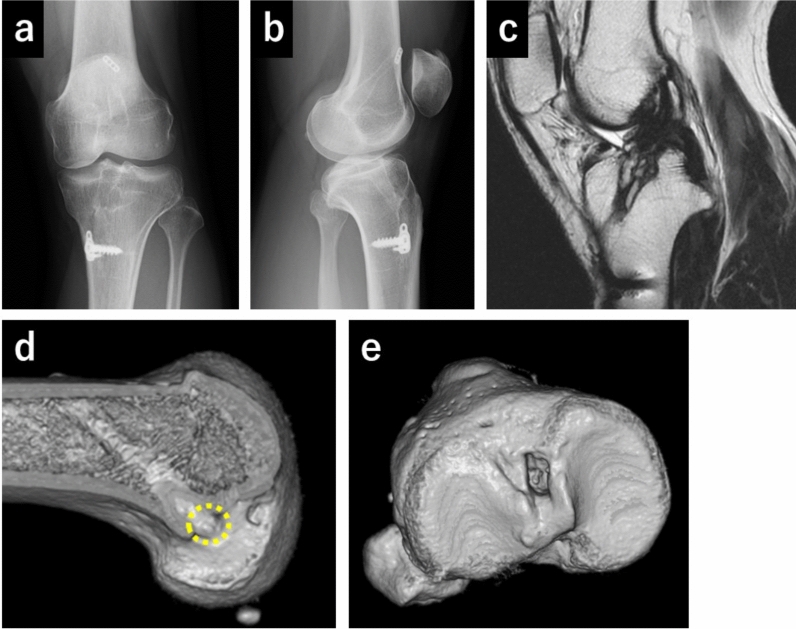

Background: Nonanatomical anterior cruciate ligament (ACL) reconstruction occasionally induces ACL failure without an evident injury episode, necessitating revision surgery. Although the in vivo kinematics of ACL deficiency before primary ACL reconstruction are well documented, the kinematics of ACL failure after nonanatomical reconstruction remain unexplored. The aim of this study is to investigate ACL failure kinematics following nonanatomical reconstruction.

Patients and methods: This study enrolled three patients with ACL failure after nonanatomical reconstruction, 20 normal and 16 ACL-deficient knees. The anteroposterior (AP) translation of the medial and lateral femoral condyles and center of the femur and femoral rotation relative to the tibia during squatting were evaluated using a two- to three-dimensional registration technique under fluoroscopy.

Results: Medial AP translation of the nonanatomically reconstructed knee in one patient showed posterior location and abnormal kinematics compared with the ACL-deficient knees. In contrast, the lateral AP position of the nonanatomically reconstructed knees in two patients were more posteriorly located and showed more abnormal kinematics than the ACL-deficient knees. Central AP translation of the nonanatomically reconstructed knees in two patients was located more posteriorly throughout the range of midflexion. Femoral rotation of the nonanatomically reconstructed knees showed abnormal kinematics compared with that of the normal and ACL-deficient knees.

Conclusions: By independently assessing the medial and lateral aspects of the femur, the medial or lateral condyle of the femur of nonanatomically reconstructed knees exhibited a more pronounced abnormality compared with ACL-deficient knees. The femur of the nonanatomically reconstructed knees showed abnormal rotational kinematics. Considering the kinematic aspect, nonanatomical ACL reconstruction should be avoided.